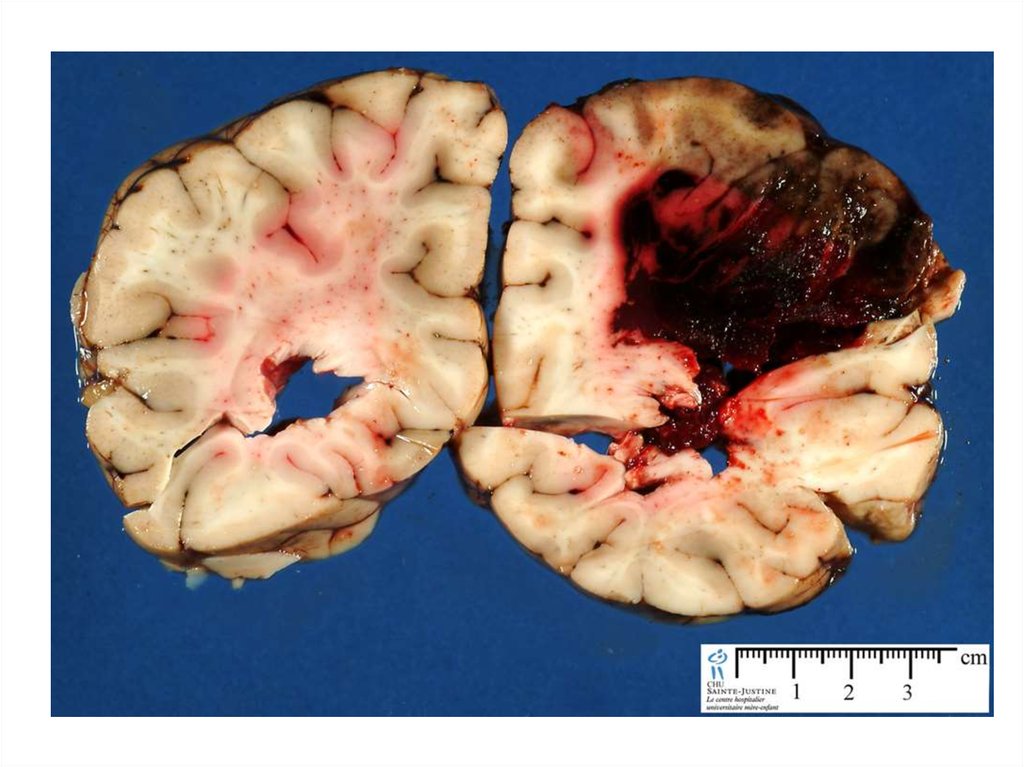

43. Артериовенозные мальформации

• Наблюдаются у 4% популяции, но

только у 12% наблюдаются клинические

проявления

• 38-70% манифестируют в виде

кровоизлияний

• Другие симптомы: обмороки, головная

боль, эпилепсия, неврологический

дефицит

44.

45.